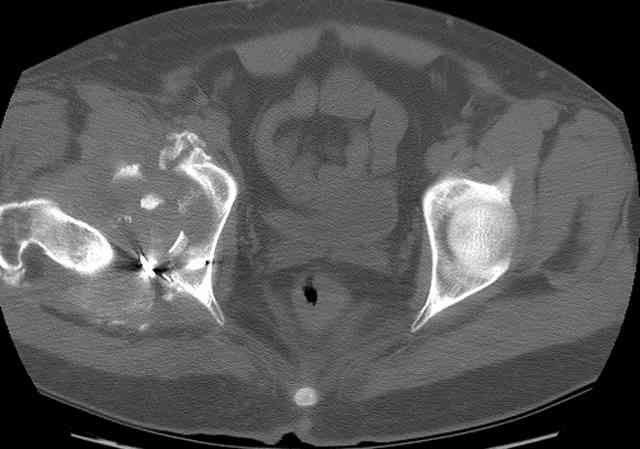

Stabilize anterior column with fluoroscopically guided screw across this end of the transverse fx - As usual, after your reduction of the femoral head, the transverse fx became minimally displaced - slightly gapped without stepoff. I usually (reduce &) stabilize the medial side of the posterior column (transverse fx) with a short plate - before placing the anterior screw unless the transverse fx is undisplaced.

Biggest problem appears to be impaction & comminution of the posterior wall fx site - you've left out some CT cuts. This is not just fragments in joint. It may leave a deficient area, &/or block satisfactory posterior wall reduction.